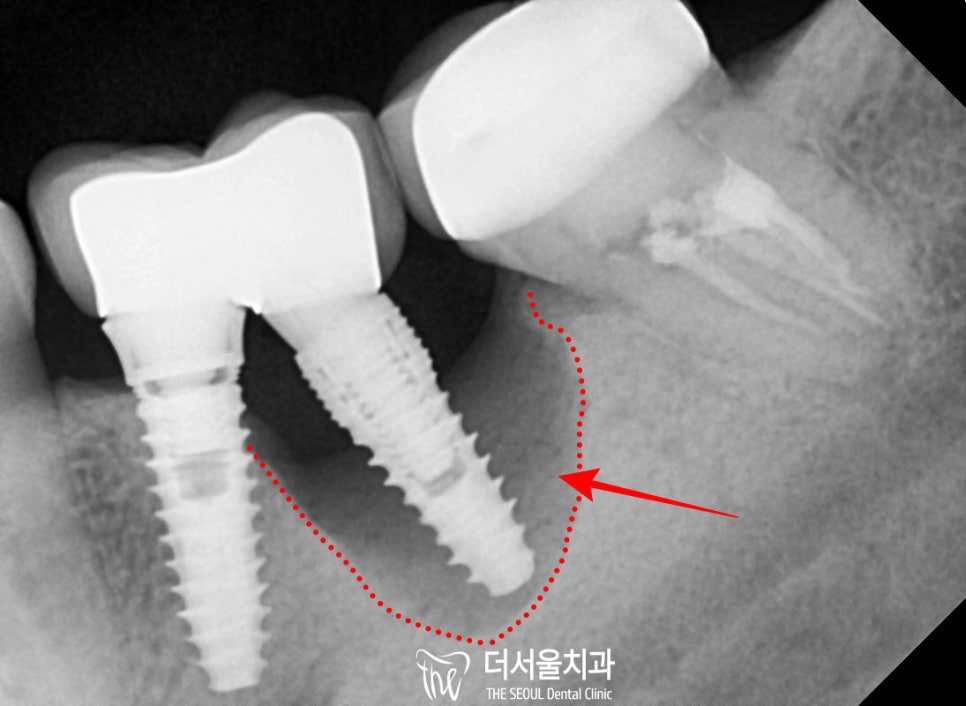

치근단 사진을 찍어서

더 정확히 살펴보면

#34, 35 중

#35 픽스처 주변의 잇몸뼈가 모두

심각하게 녹아있었습니다.

3. 치조골 소실 원인

아마도 태평역 치과 에서 예상하건대

이전에 픽스처 식립을 할 때

식립 각도가 조금 기울어있다 보니

브릿지 하방으로 음식이

심하게 끼어 관리가 잘 안되었던 것 같습니다.

또한 이와 동시에

#35의 픽스처가 현재는

잇몸 속에 묻혀있어

잘 보이지 않으나

치조골 내에서 찢어져있을

가능성도 있습니다.

그러다 보니 하나의 픽스처 주변으로

치태가 쌓이고 세균이 감염을 일으키면서

골소실을 유발한 것 같습니다.